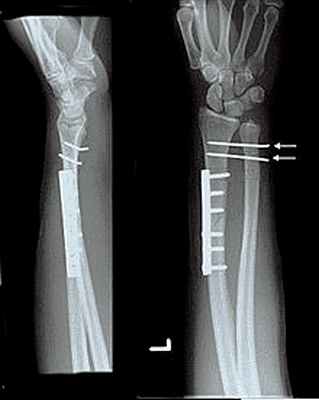

Перелом лучевой кости с вывихом головки локтевой кости (перелом Галеацци) • Причины: падение на вытянутую руку, удары по предплечью • Патоморфология: лучевая кость ломается в нижней трети, её отломки смещаются кпереди (дистальный отломок дополнительно занимает положение пронации из-за сокращения мышц), образуя угол, открытый кзади; головка локтевой кости смещается в ладонную или тыльную сторону • Клиническая картина: характерная деформация (западение на тыльной поверхности предплечья с лучевой стороны и выпячивание на ладонной), искривление оси лучевой кости, пальпируется головка лучевой кости на локтевой стороне лучезапястного сустава, болезненность при пальпации и осевой нагрузке. Надавливание на головку лучевой кости вызывает вправление, при прекращении давления головка снова вывихивается. Необходимо проводить в обязательном порядке рентгенографию с захватом лучезапястного сустава • Лечение: репозиция, гипсовая повязка на 8–10 нед, при неэффективности консервативного лечения — открытая репозиция и остеосинтез лучевой кости, открытое вправление головки локтевой кости.

Остеосинтез лучевой/локтевой кости пластиной

После выставления отломков в правильное положение металлическая пластина фиксируется на кости с помощью специальных винтов, не давая отломкам сместиться. Если сломаны и лучевая, и локтевая кость, устанавливается две пластины. После операции на руку накладывается защитная гипсовая лонгета, в среднем – на 2-3 недели. Средний срок госпитализации при подобном оперативном вмешательстве – 7 дней. После выписки необходимо делать перевязки в амбулаторном режиме (в поликлинике). Через 2-3 недели лонгета снимается, и назначается курс восстановительного лечения – лечебная физкультура, физиотерапия. Пластины удаляются в среднем через год.